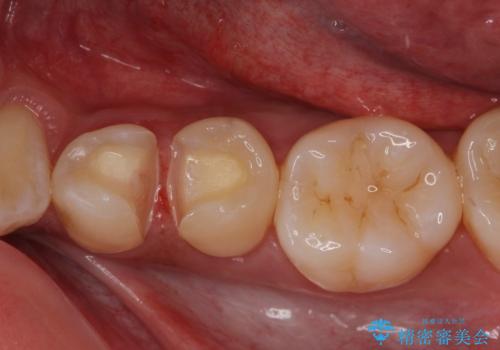

- 矯正前の患者様です。検査により虫歯がありましたのでe-maxインレー治療を行いました。

- e-maxインレー 7.7万×2費用は治療当時の料金となります